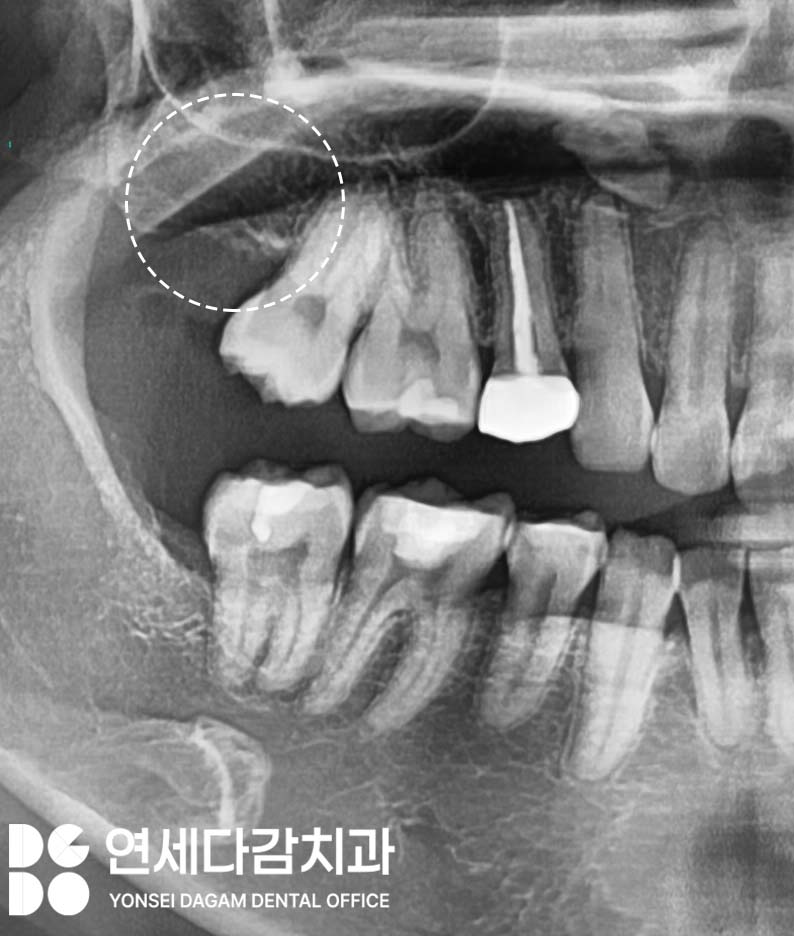

CT를 분석한 이후에는

치료 부위 주변의 잇몸을 절개하고

뼈를 정리합니다.

근심으로 기울어져 있는 사랑니는

한 덩어리로 나오기 힘들기 때문에

조각으로 분리합니다.

이를 뺀 뒤에는 남아있는

조각은 없는지 확인하고 마무리하게 됩니다.

만약

이를 빼는 과정에서 천공이 일어났다면

콜라겐 멤브레인을 통해

적절한 폐쇄술을 시행하고

봉합하여 대처할 수 있습니다.

작은 천공의 경우 자연 치유가 가능하지만,

큰 천공이나 지속적인

구강-상악동 누공이 발생한 경우에는

추가적인 외과적 처치가

필요할 수 있습니다.